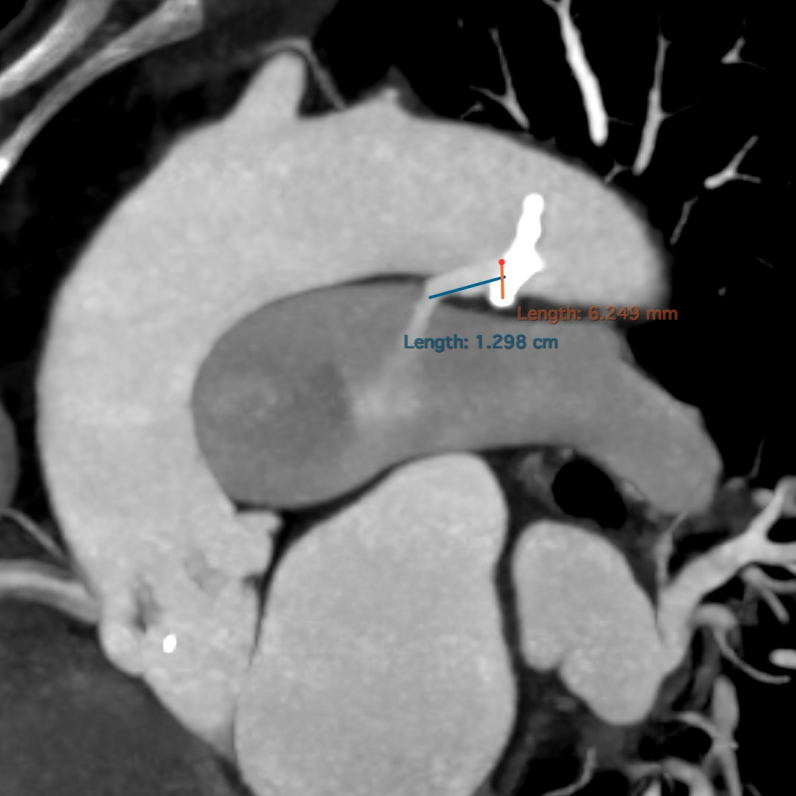

CT评估

• CT显示分布的四叶瓣,瓣窦较小,冠脉开口较低,瓣叶冗长增厚,左右冠瓣叶长度均超过STJ高度。

• CT术前预估冠脉遮挡风险较高,术者团队计划Downsize选择人工瓣膜尺寸,植入21mm瓣膜,并对冠脉进行预保护,进行TAVR术治疗。

术前发现患者合并动脉导管未闭

管型6.2mmx12.9mm